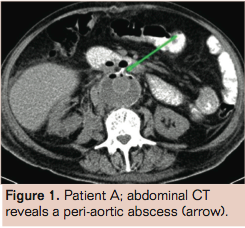

Patient A is a 78-year-old male with a history of Billroth 1 gastric resection, coronary artery bypass grafting, lung carcinoma (T1N0M0 treated with radiotherapy), a venous supragenual femoral-popliteal bypass, percutaneous transluminal angioplasty, chronic obstructive pulmonary disease GOLD 2, hypertension, and hypercholesterolemia. He presented with a ruptured aneurysm of the abdominal aorta with a diameter of 7.0 cm on computed tomography (CT) angiography with no signs of infection or inflammation. Emergency open aneurysm repair was performed with a Dacron prosthesis (DuPont). After surgery, he was admitted to the intensive care unit (ICU) for 2 days where he developed pneumonia (Escherichia coli), which was treated with ceftriaxone, a broad-spectrum cephalosporin. At return to the vascular surgical ward, fever persisted. Common postoperative causes of infection were ruled out. CT angiography showed intraperitoneal and retroperitoneal abscesses (Figure 1). CT-guided puncture of only the periprosthetic hematoma was performed. The other abscesses were not punctured and drained. Culture revealed a Listeria monocytogenes. Although L monocytogenes infection is commonly seen in patients with close contact to milk and cheese products, our patient had no history of eating or working with these products. The graft infection was discovered 2 weeks after initial operation, and was considered an unfavorable period for a relaparotomy. We believed graft removal was not feasible in this patient because of his poor nutritional status, recent pneumonia and recent postoperative status. Therefore we started conservative treatment. Antibiotics were switched to amoxicillin and gentamicin, according to sensitivity of the cultured micro-organism and administered intravenously during 6 subsequent weeks. Control abdominal CT showed a reduction of the abscesses (Figure 2). Blood levels of C-reactive protein (CRP) returned toward a normal value of 6 mg/L. The patient was discharged after a hospital stay of 61 days, with continuation of amoxicillin by mouth. An abdominal CT scan 15 months after discharge showed no signs of infection.